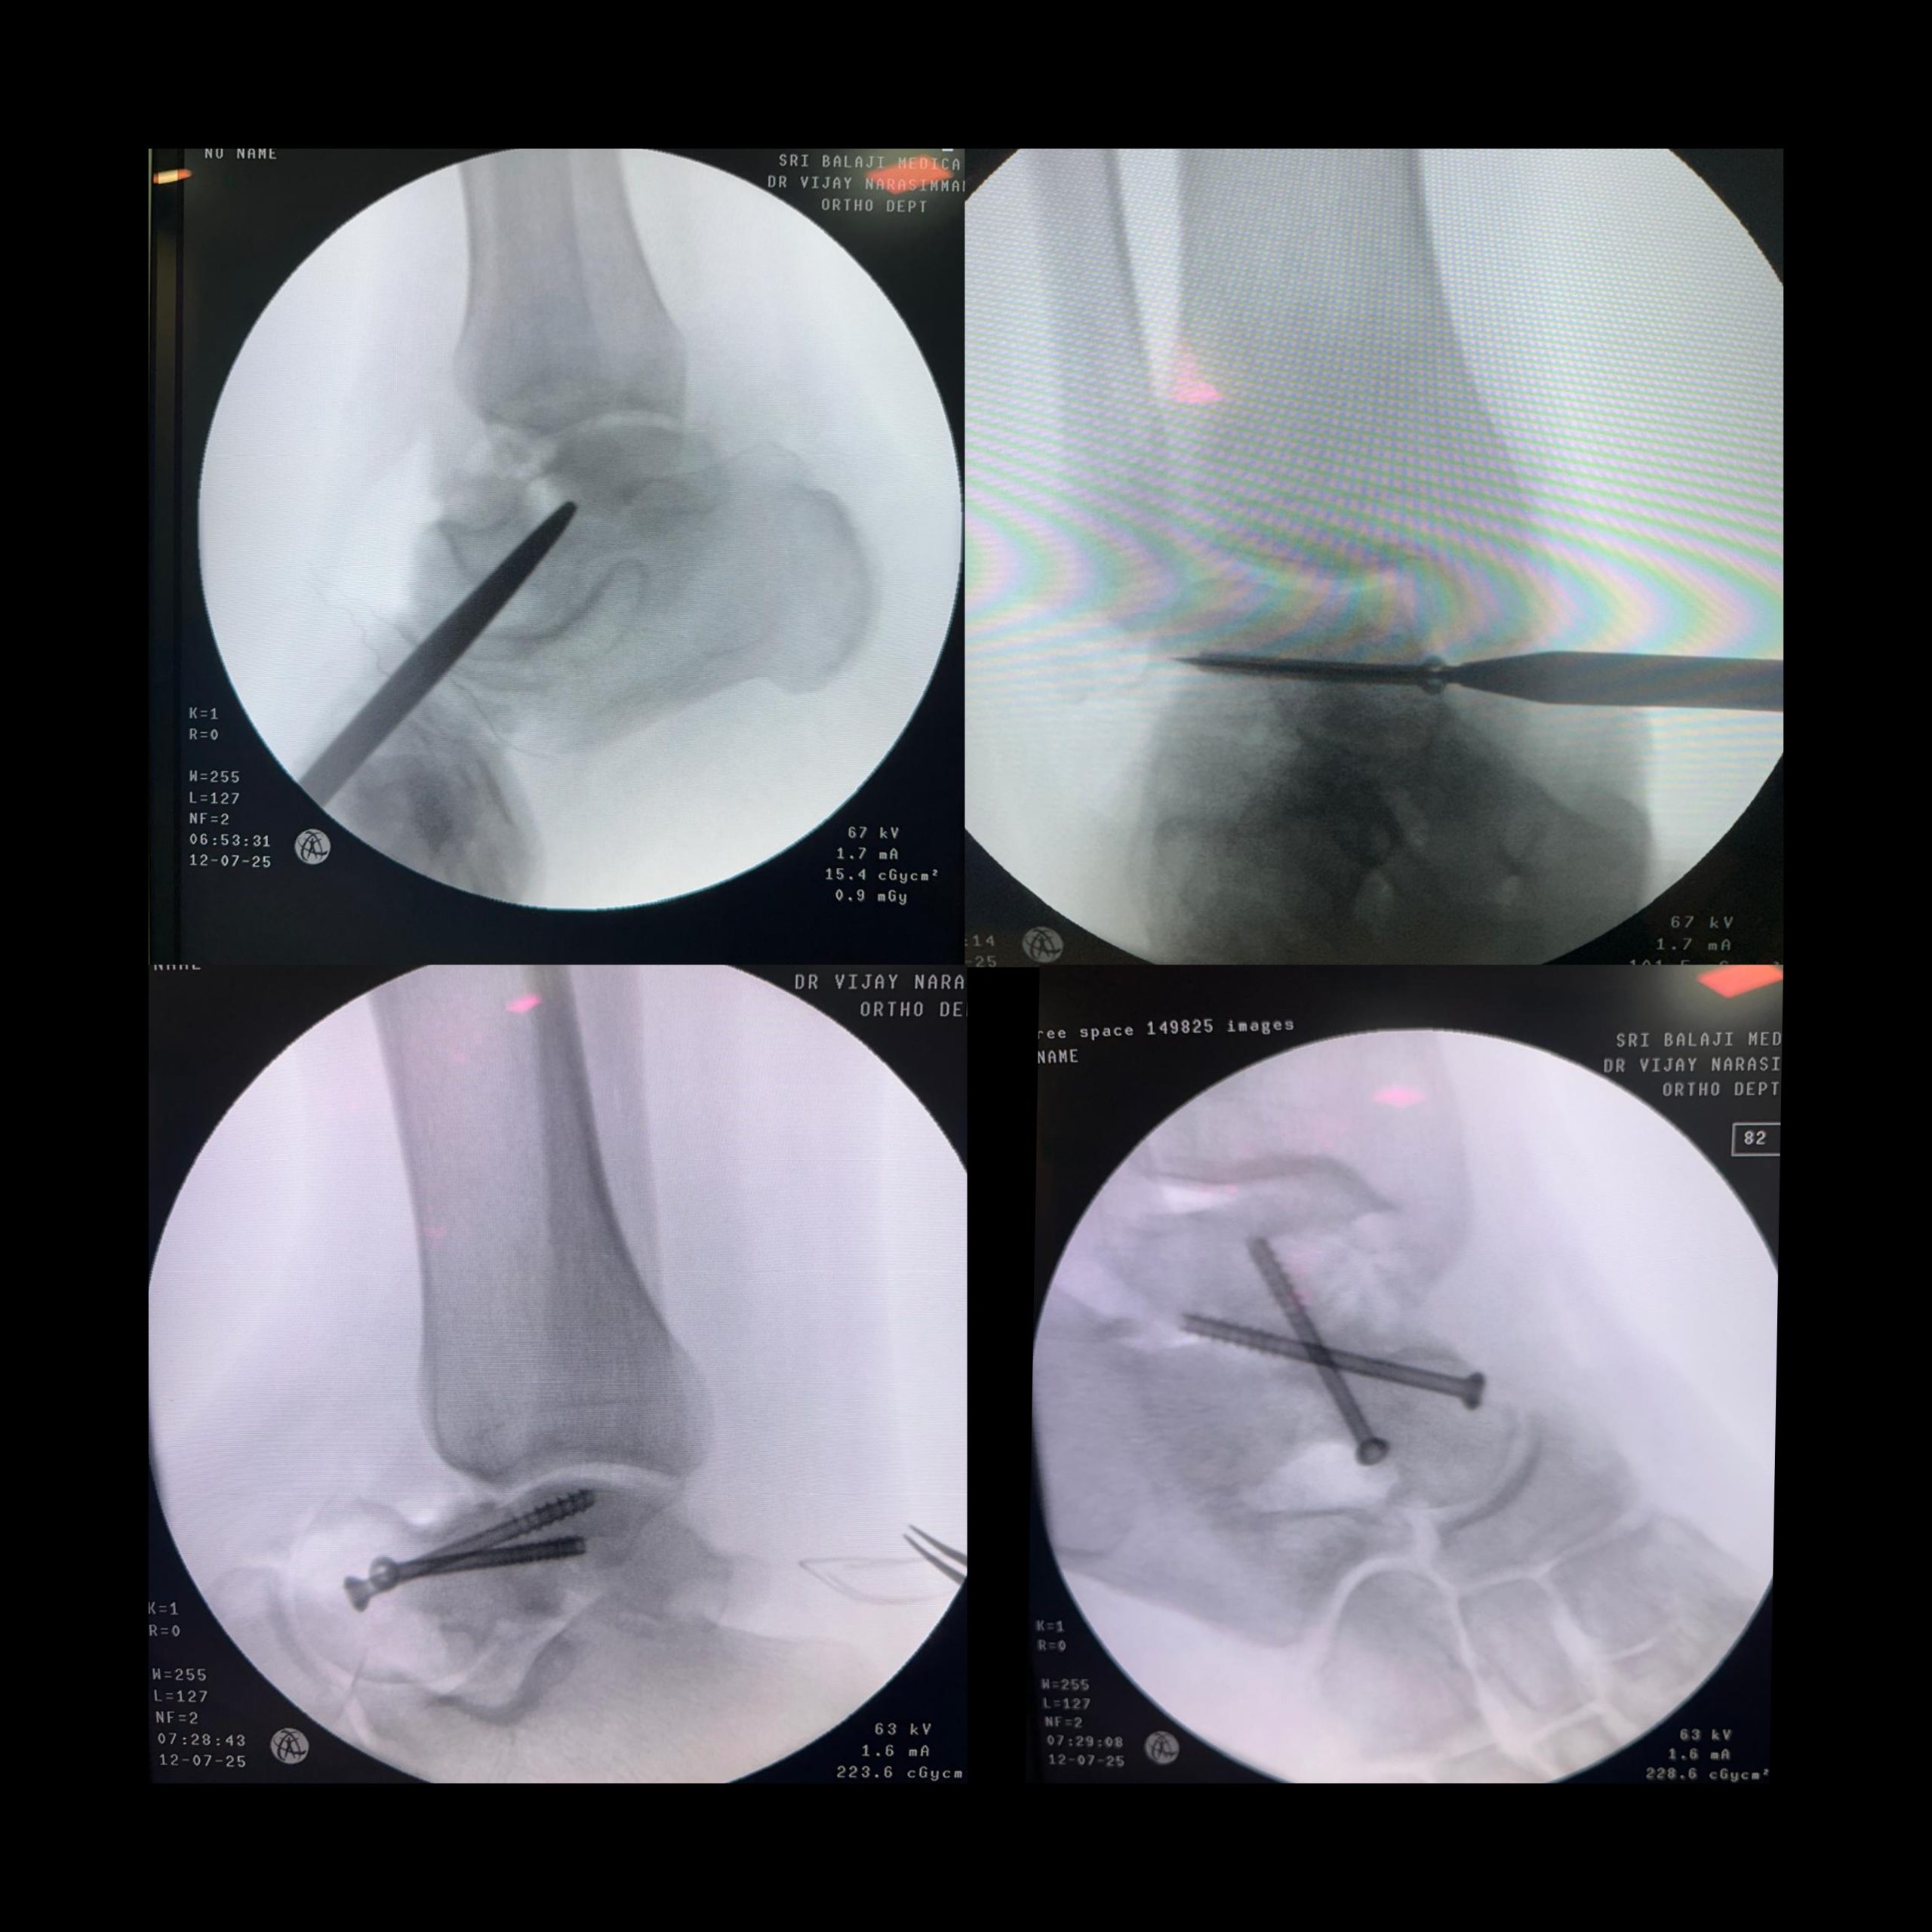

After detailed counseling, the patient was taken up for open reduction and internal fixation (ORIF) under spinal anesthesia. A standard anteromedial approach and anterolateral approach were used (Fig. 4).

Figure 4: Pre-operative clinical picture.

Fibrous tissue and sclerotic bone at the fracture site were debrided to healthy bleeding bone ends. Anatomical reduction was achieved, and fixation was done using two 4.0 mm cannulated cancellous screws inserted in a lag fashion under fluoroscopic guidance [6] (Fig. 5).

Figure 5: Intraoperative C-arm images.